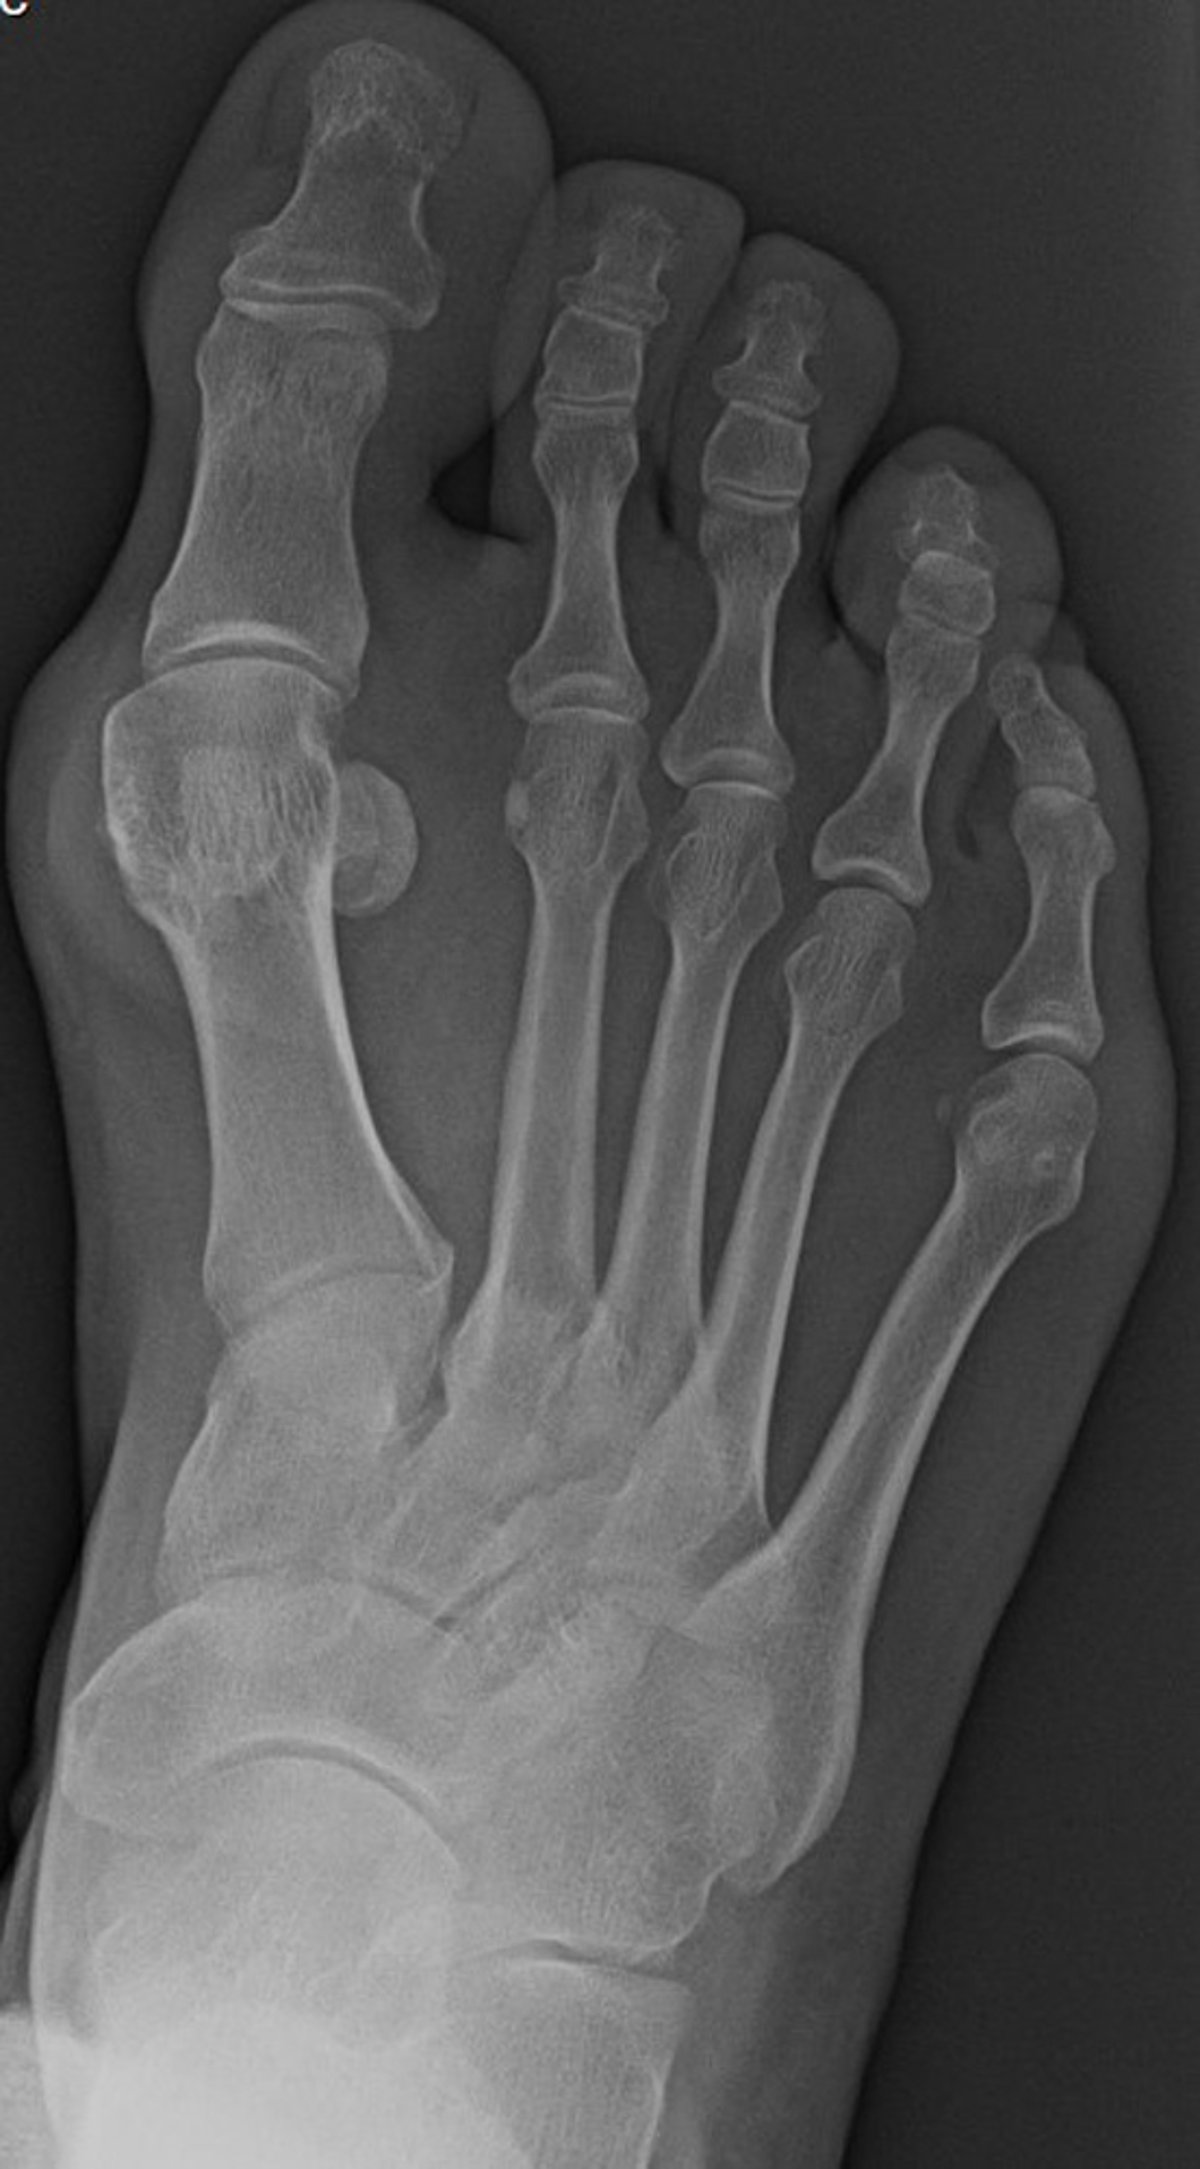

Radiographie de face du pied avec un hallux valgus

Cette incidence de face du pied montre des signes radiographiques compatibles avec un hallux valgus, avec déviation médiale du premier métatarsien. Il existe également une subluxation latérale de la base de la première phalange proximale par rapport à la tête du premier métatarsien.

Image courtoisie de James C. Connors, DPM.